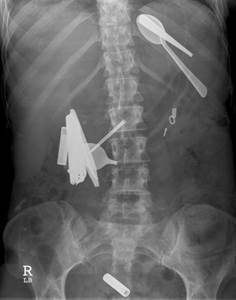

УЗИ брюшной полости обычно может дать только косвенные данные о предполагаемом наличии инородного тела в желудке у собаки. Для диагностики инородного предмета в желудке используется рентгенография, но она информативна для рентгенконтрастных предметов (металл, кости, камни и т.д.). В некоторых случаях будет информативна рентгенография с применением контраста (тряпки и им подобные материалы будут удерживать контрастное вещество). Точную информацию о наличии инородного тела в желудке и о состоянии стенок желудка даст гастроскопия.